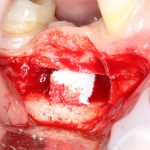

Откроем область операции и посмотрим, что там:

Вроде как, всё неплохо. Наверное, можно поставить имплантаты?

ну, или как-то так:

При этом, я хотел бы обратить ваше внимание на один важный момент. То, с чем вы сейчас работаете — не кость, в привычном нам гистолого-физиологическом понимании. Это костная мозоль вперемежку с графтом. Её свойства довольно сильно отличаются от того, что мы привыкли называть костной тканью. Поэтому при установке имплантатов соблюдайте максимальную осторожность и щадящий режим. Никаких диких торков, усилий, больших переходов между размерами фрез допускать нельзя. Будьте аккуратны.